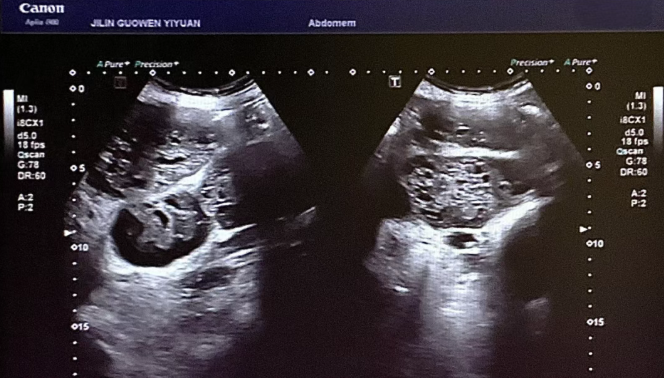

患者錢女士(化名),65 歲,因有高血壓病史而定期進(jìn)行體檢。在超聲檢查時(shí),醫(yī)生發(fā)現(xiàn)其腎臟存在占位性病變。超聲科團(tuán)隊(duì)借助高分辨率超聲成像技術(shù),清晰地觀察到腎臟內(nèi)的異常回聲區(qū),再結(jié)合血流信號分析,高度懷疑該病變可能為惡性腫瘤。為進(jìn)一步明確診斷,團(tuán)隊(duì)在超聲引導(dǎo)下進(jìn)行精準(zhǔn)穿刺,獲取病理組織。最終,病理報(bào)告確診該病變?yōu)?“小圓細(xì)胞惡性腫瘤”。

小圓細(xì)胞惡性腫瘤是一類較為少見的惡性疾病,常見于兒童及青少年,而發(fā)生在老年患者腎臟的情況則更為罕見。此類腫瘤具有很強(qiáng)的侵襲性,早期診斷對于治療方案的制定以及患者的預(yù)后都至關(guān)重要。錢女士雖然沒有出現(xiàn)典型癥狀,腹部查體也未觸及包塊,但得益于超聲科的細(xì)致檢查,病灶被及時(shí)發(fā)現(xiàn),這為后續(xù)的治療贏得了寶貴時(shí)間。